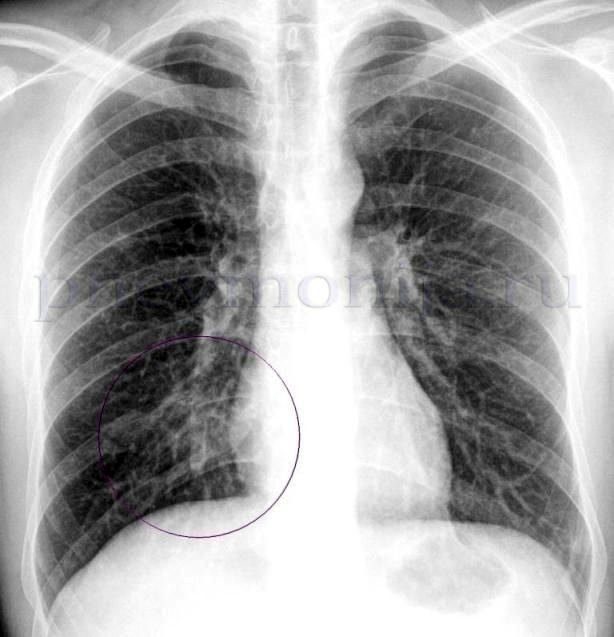

Диагноз основывается на симптомах острой инфекции дыхательных путей и наличии затемнения при рентгенологическом исследовании органов грудной полости, которое не связанное с какой-либо другой причиной (например, кардиогенный отек легких).

- рентгенографию органов грудной клетки – выявляет затемнение ткани легкого;

| M (multilobar infiltration) | Мультилобарная инфильтрация на рентгенограмме легких | 1 |